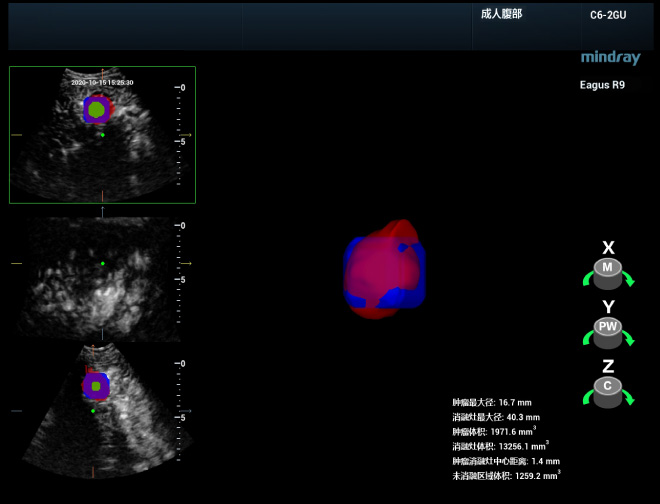

Ofrecer un diagnĂłstico clĂnico con mayor precisiĂłn

Realizar una evaluaciĂłn completa e inmediata despuĂ©s de la ablaciĂłn es vital para detectar tumores residuales y realizar un tratamiento complementario de inmediato, lo que ayuda a mejorar la tasa de ablaciĂłn completa y evitar la apariciĂłn de un avance local. El equipo de la profesora Xie puede realizar una ultrasonografĂa 3D del sitio de la ablaciĂłn inmediatamente despuĂ©s del procedimiento y luego fusionarla con los datos de la ultrasonografĂa 3D para obtener una imagen completa que indique si el sitio de la ablaciĂłn cubre el lĂmite seguro de la lesiĂłn en todo el espacio 3D y si hay alguna lesiĂłn residual o una ablaciĂłn insuficiente. AdemĂĄs, se pueden llevar a cabo una visualizaciĂłn de segmentaciĂłn tomogrĂĄfica y una reconstrucciĂłn del volumen 3D de esta imagen de fusiĂłn para ver mĂĄs claramente la ubicaciĂłn espacial del ĂĄrea que necesita tratamiento complementario y su relaciĂłn con los Ăłrganos vitales circundantes.